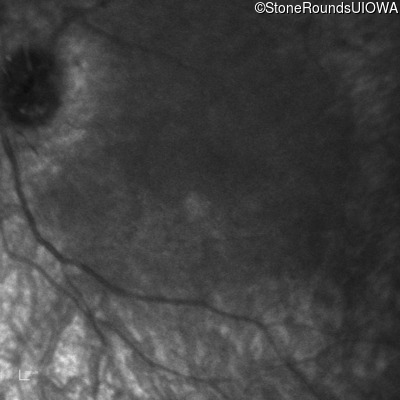

Infrared Fundus Photograph - Right -

No Light Perception

Infrared Fundus Photograph - Left -